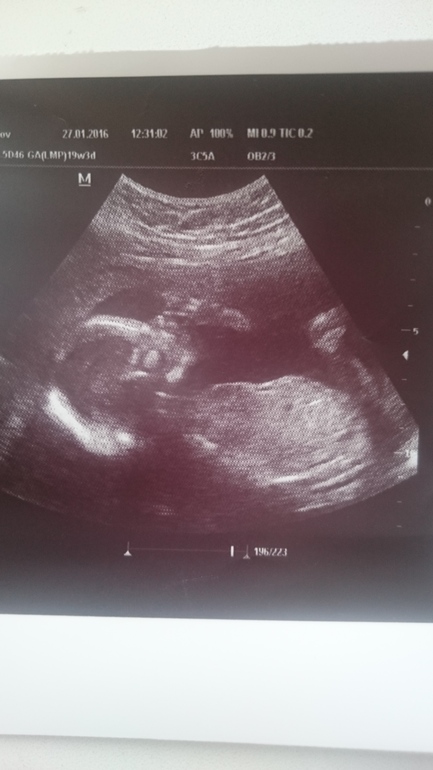

ну и напоследок моя младшенькая крошка))здесь нам ещё 20 неделек и она очень усердно сосёт пальчик)))вкусный наверно)))